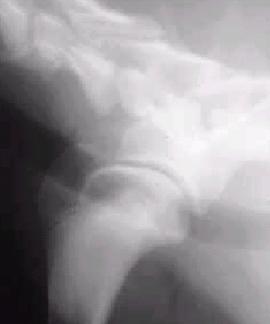

Câine: 8 luni mascul, rasă Dog german

Debutul bolii in urmă cu 2-3 saptamâni. Animalul schiopătă uneori de piciorul drept anterior. schiopatura alterneaza cu intervale de timp în care mersul este normal (1-2 zile) apoi revine la un mers schiopatat.

S-a apelat la medic care, timp de o saptamâna, a administrat antiinflamatorii. În perioada tratamentului s-a observat o îmbunatatire, dupa care schiopatura a revenit.

Examen clinic

Temperatură 38,3oC, Frecventa cardiacă 113, Frecventa respiratorie 26

schiopatura de gradul I-II. Usoară atrofie a muschilor spetei.

Manipularea membrului cu producerea unor miscari de hiperflexie-hiperextensie produce constant durere, uneori poate fi auzit si un zgomot specific de clic-clac.

Cerinte suplimentare – examen radiologic (pentru articulatia scapulo-humerala)

Diagnostic – osteocondrita disecanta